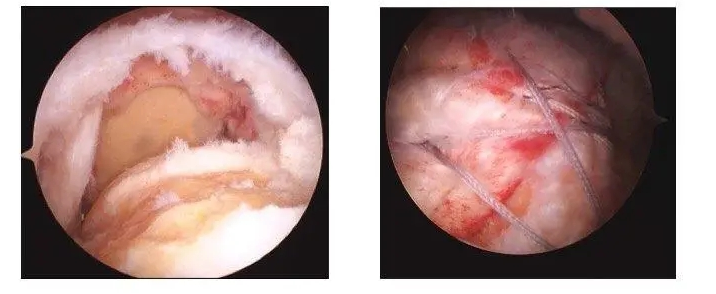

鏡下圖片

案例:患者吳某,女,62歲,因右肩部(bù)疼痛、活(huó)動受限3個月(yuè)入(rù)院治療。MRI示:右肩(jiān)袖損傷,岡上肌肌(jī)腱斷(duàn)裂,右肩關節退行性改變。入院後完善相關(guān)輔助檢查,在全麻下(xià)+臂叢(cóng)麻醉下行右肩關節鏡下肩袖(xiù)修補術,患(huàn)者術後肩部疼痛明顯緩解(jiě),手術切口小、恢複快,指導患者功能鍛煉,術後第三天康複出院,患(huàn)者對治療效果很滿(mǎn)意。

肩袖(xiù)損傷是臨床上常見的疾病,是指肩關節周圍組織,即岡上肌、岡下肌、小圓肌以及肩胛肌損傷(shāng),臨床主要以疼痛為主,特(tè)別是側臥時,疼痛感嚴重加劇,可引起患者(zhě)功能障礙,影響患者生(shēng)活質量。肩袖損傷疾病主要好發於中老年群體(tǐ)或者是長期從(cóng)事體力勞動者,出現此病的原因是由於肩關節組織(zhī)發生結構磨損,引起此病最主要的因素的是(shì)肩關節撞擊綜(zōng)合征,且岡上(shàng)肌損傷是此病(bìng)常見的表現。肩袖損傷具較(jiào)高的發病(bìng)率,且誤診率偏高,臨床表現夜間疼痛、伴隨肩部乏力、肌力減弱等,且患者運(yùn)動時同樣會伴隨強烈劇痛感。隨著微創技術的發展以及進步,選擇肩關節鏡手術治療此病效果良好(hǎo),具有創(chuàng)傷小、疼痛(tòng)感較低、術中(zhōng)出血量少(shǎo)、術後並發症少、肩關節恢複(fù)速度快等優勢。武(wǔ)寧縣人(rén)民醫院骨科已順利開展關節(jiē)鏡下肩袖修(xiū)補術(shù),且取得較好效果,患者住院周期(qī)為5-7天,創(chuàng)傷小、疼痛感較(jiào)低、恢複(fù)快。